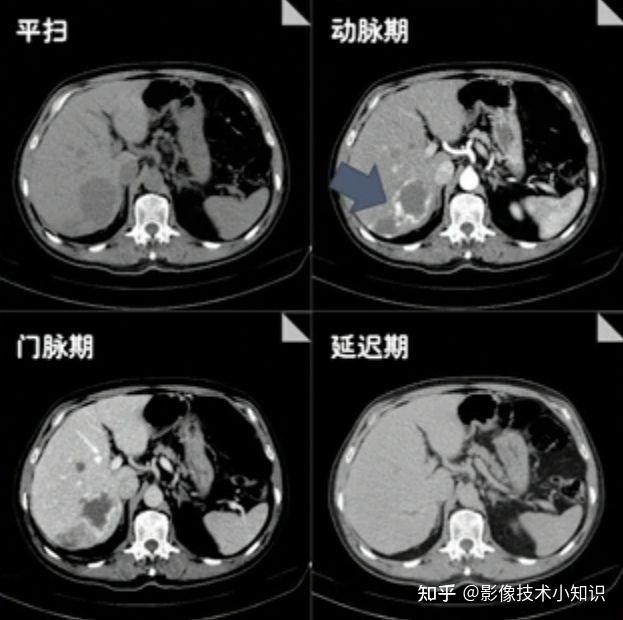

肝海绵状血管瘤的影像诊断

目前,影像学检查(如b超,ct,mri)是诊断肝血管瘤的主要方法